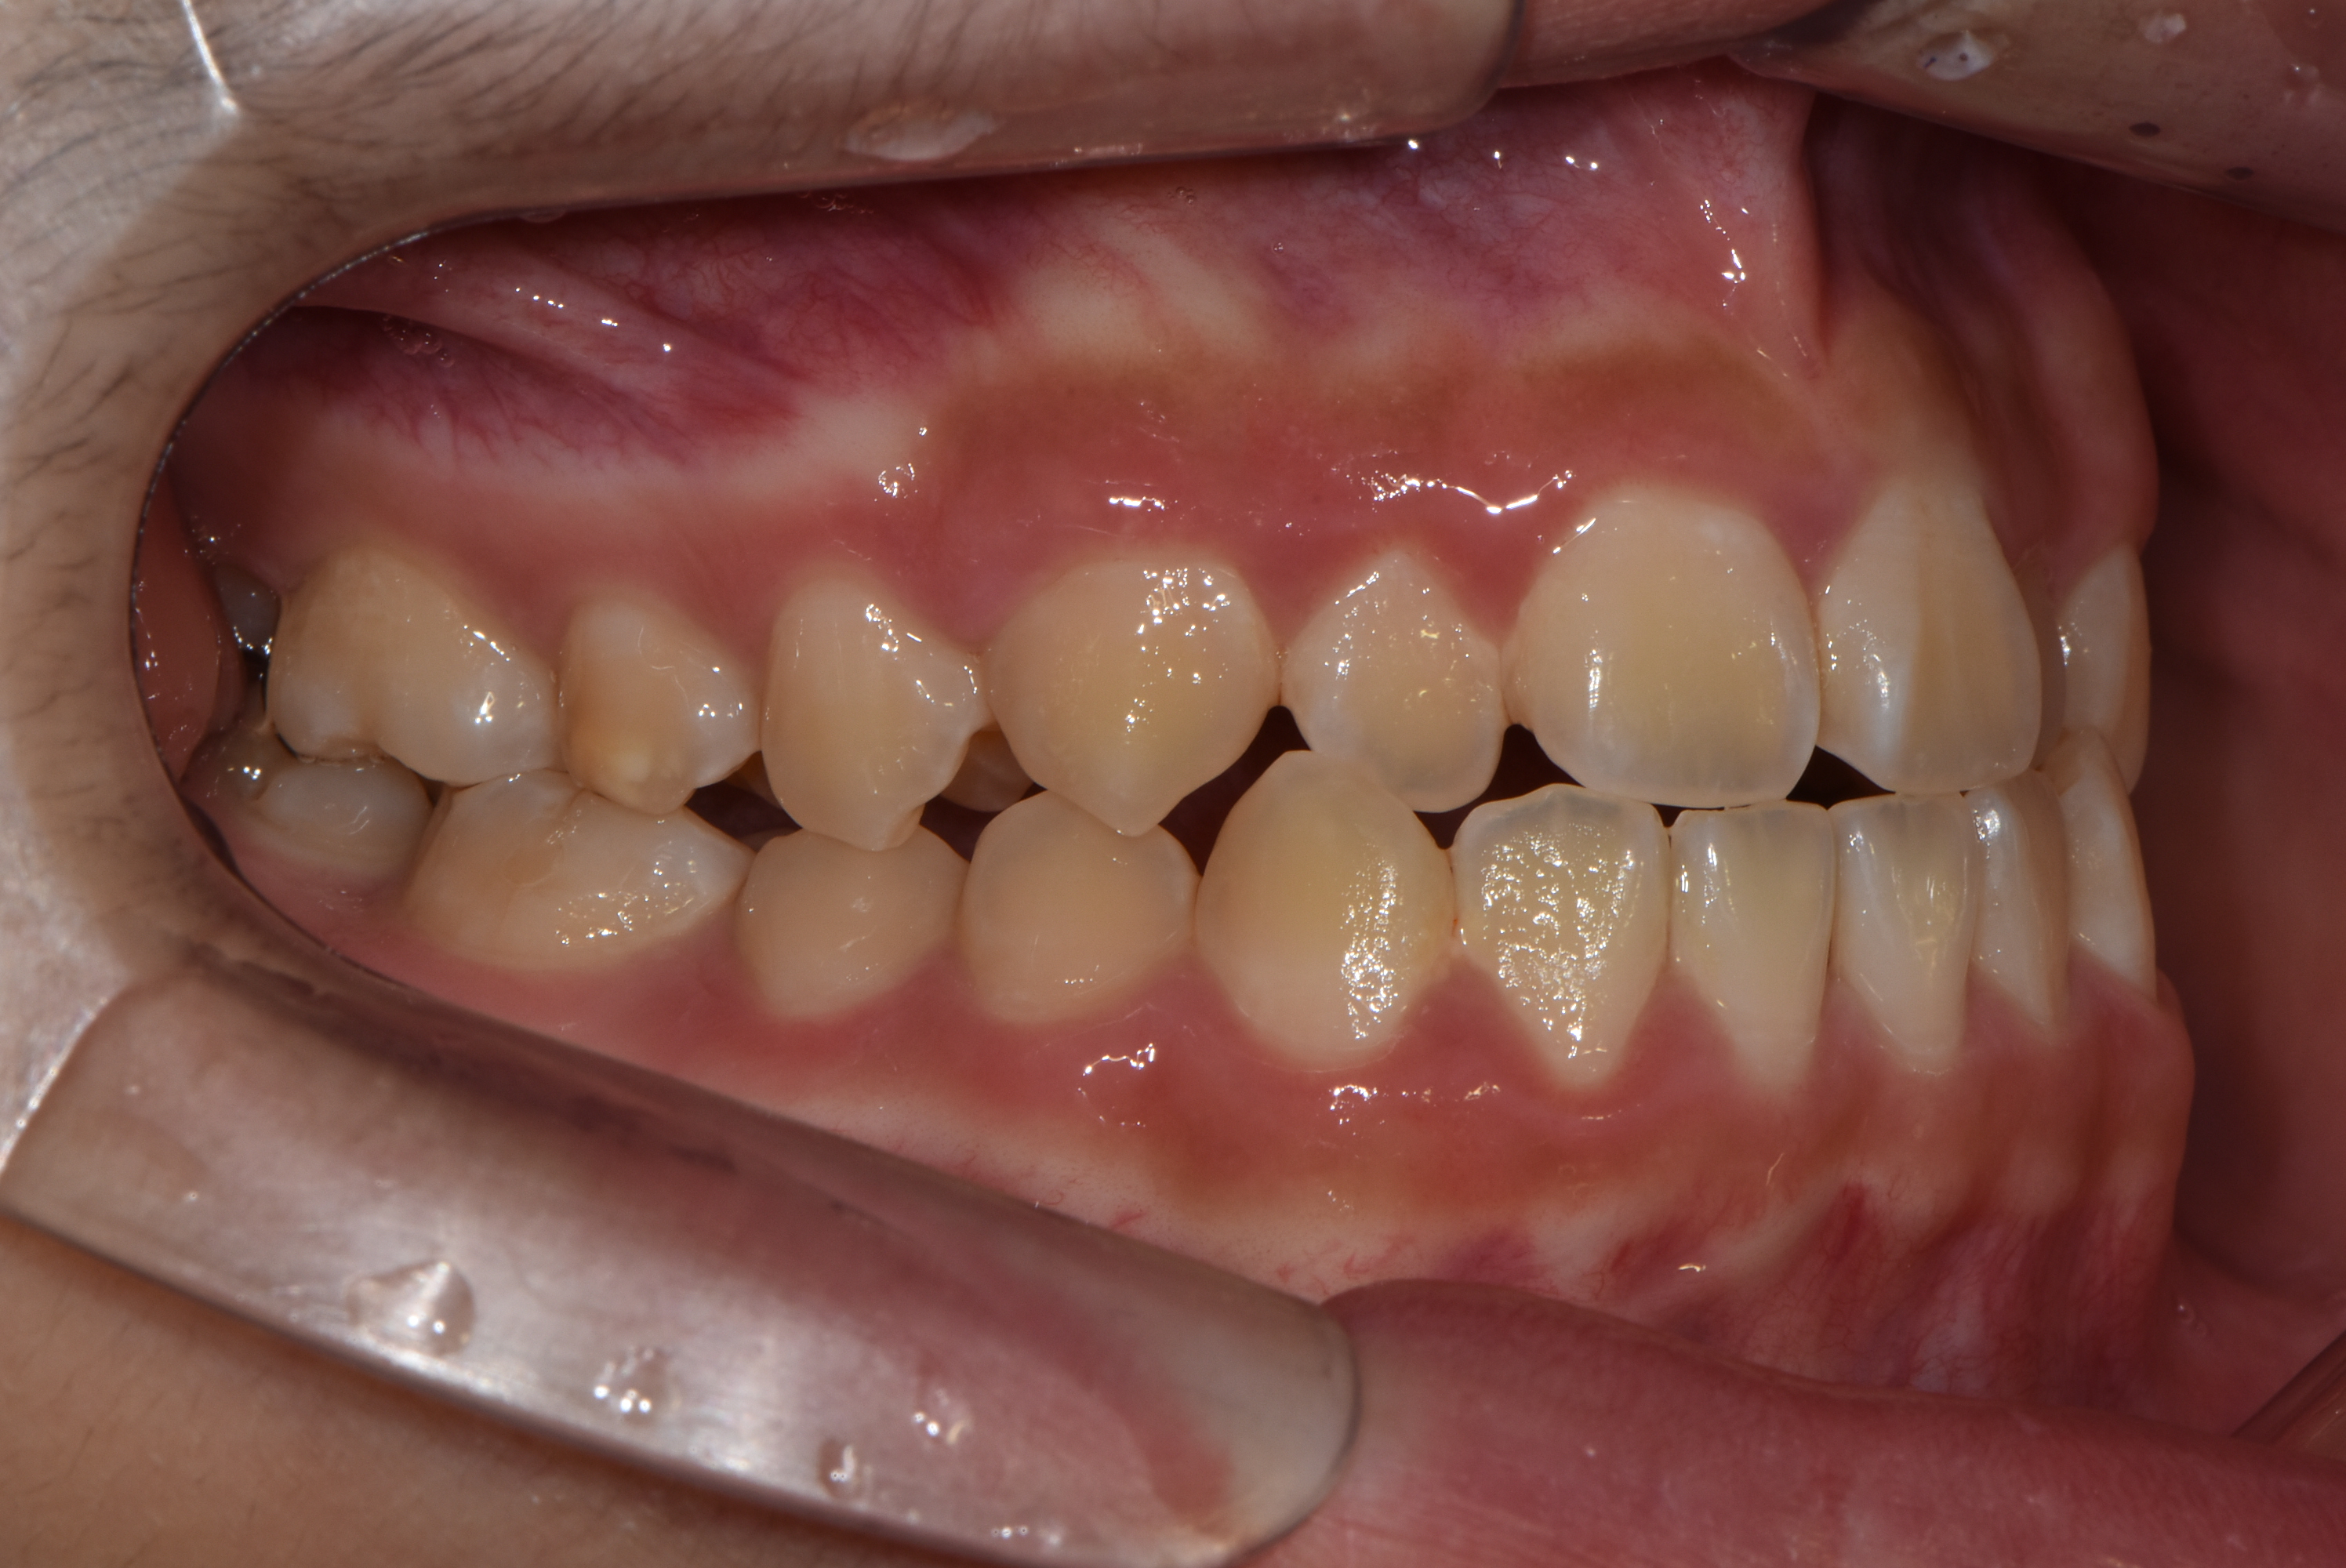

치료 전 사진입니다.